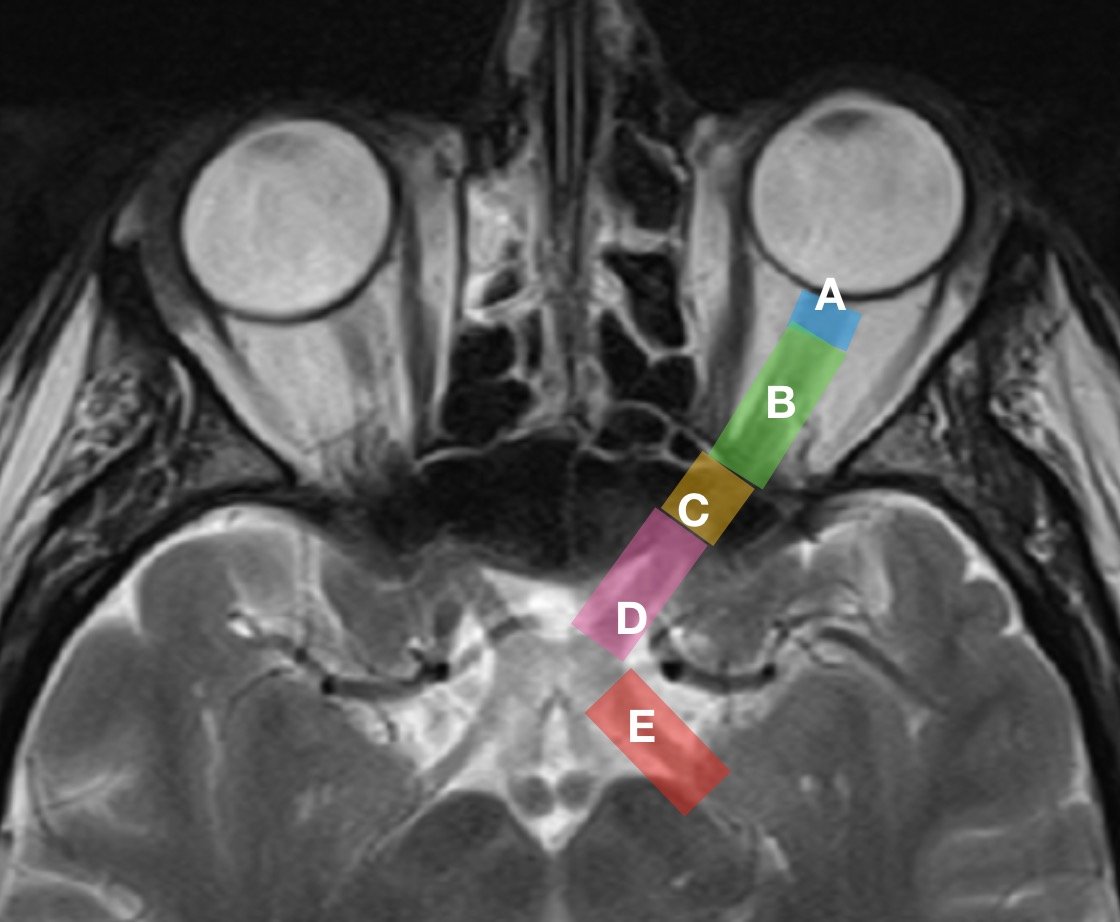

Optic Nerve In Eye. For this reason, the optic nerve is also called the second cranial nerve or cranial nerve ii. the optic nerve, also known as the cranial nerve ii, is a bundle of nerve fibers that carry visual information from. The optic nerve is located in the back of the eye. It’s comprised of four parts: Learn about its structure, role, and common diseases that can affect it and cause vision problems. the optic nerve is a bundle of nerve fibers that transmits visual information from the eye to the brain. the optic nerve is the nerve that carries information from the eye to the brain. one of the most important nerves in the upper body, the optic nerve connects the eyeball and the brain. It’s responsible for carrying messages between the eye and brain. It’s the second of 12 cranial nerves, which include the olfactory nerve, oculomotor nerve, facial nerve and others. It is also called the second cranial nerve or. Intraocular, intraorbital, intracanalicular, and intracranial.

The optic nerve is located in the back of the eye. It’s comprised of four parts: the optic nerve is the nerve that carries information from the eye to the brain. It is also called the second cranial nerve or. Learn about its structure, role, and common diseases that can affect it and cause vision problems. It’s responsible for carrying messages between the eye and brain. It’s the second of 12 cranial nerves, which include the olfactory nerve, oculomotor nerve, facial nerve and others. For this reason, the optic nerve is also called the second cranial nerve or cranial nerve ii. the optic nerve, also known as the cranial nerve ii, is a bundle of nerve fibers that carry visual information from. the optic nerve is a bundle of nerve fibers that transmits visual information from the eye to the brain.

Optic Nerve In Eye It’s the second of 12 cranial nerves, which include the olfactory nerve, oculomotor nerve, facial nerve and others. It is also called the second cranial nerve or. It’s responsible for carrying messages between the eye and brain. For this reason, the optic nerve is also called the second cranial nerve or cranial nerve ii. the optic nerve is a bundle of nerve fibers that transmits visual information from the eye to the brain. one of the most important nerves in the upper body, the optic nerve connects the eyeball and the brain. The optic nerve is located in the back of the eye. Intraocular, intraorbital, intracanalicular, and intracranial. It’s the second of 12 cranial nerves, which include the olfactory nerve, oculomotor nerve, facial nerve and others. the optic nerve, also known as the cranial nerve ii, is a bundle of nerve fibers that carry visual information from. It’s comprised of four parts: Learn about its structure, role, and common diseases that can affect it and cause vision problems. the optic nerve is the nerve that carries information from the eye to the brain.